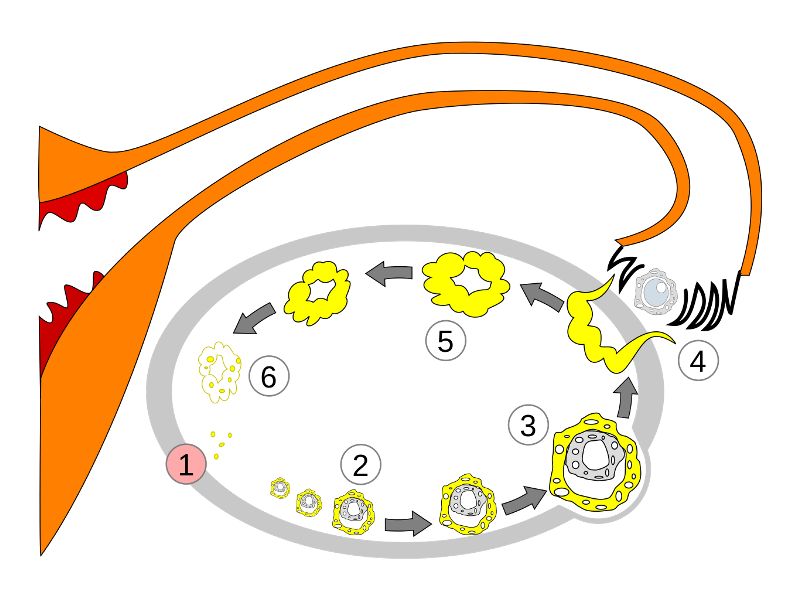

Follicular maturation

- Primordial follicle

- Growing follicle

- Primary follicle

- Secondary follicle

- Mature follicle (Graafian)

Corpus luteum

Slide 91

Corpus luteum

- Two major cell types

- Granulosa lutein cells

- modified granulosa cells

- Theca lutein cells

- modified theca interna cells

- Many capillaries

Granulosa lutein cells

- Modified granulosa cells

- Large - 30µm

- Pale cells

Theca lutein cells

- Modified theca interna cells

- Smaller - 15µm

- Dark stained

Menstrual cycle

- Follicular phase

- Luteal phase

- Menstrual phase

Follicular phase

- Epithelium reform

- Proliferation of

- Glands

- Connective tissue

- Blood vessels

- Glands become coiled

- Helical arteries 2/3 into endometrium

Luteal phase

- Thickening endometrium

- Edema

- Endometrial gland secretion

- Glands

- Glandular cells at apex

- Basal accumulation glycogen

- Helical arteries reach superficial regions

Menstrual phase

- Vasoconstriction

- Ischaemia

- Necrosis functional layer

- Basal layer

- No necrosis

- Short straight vessels